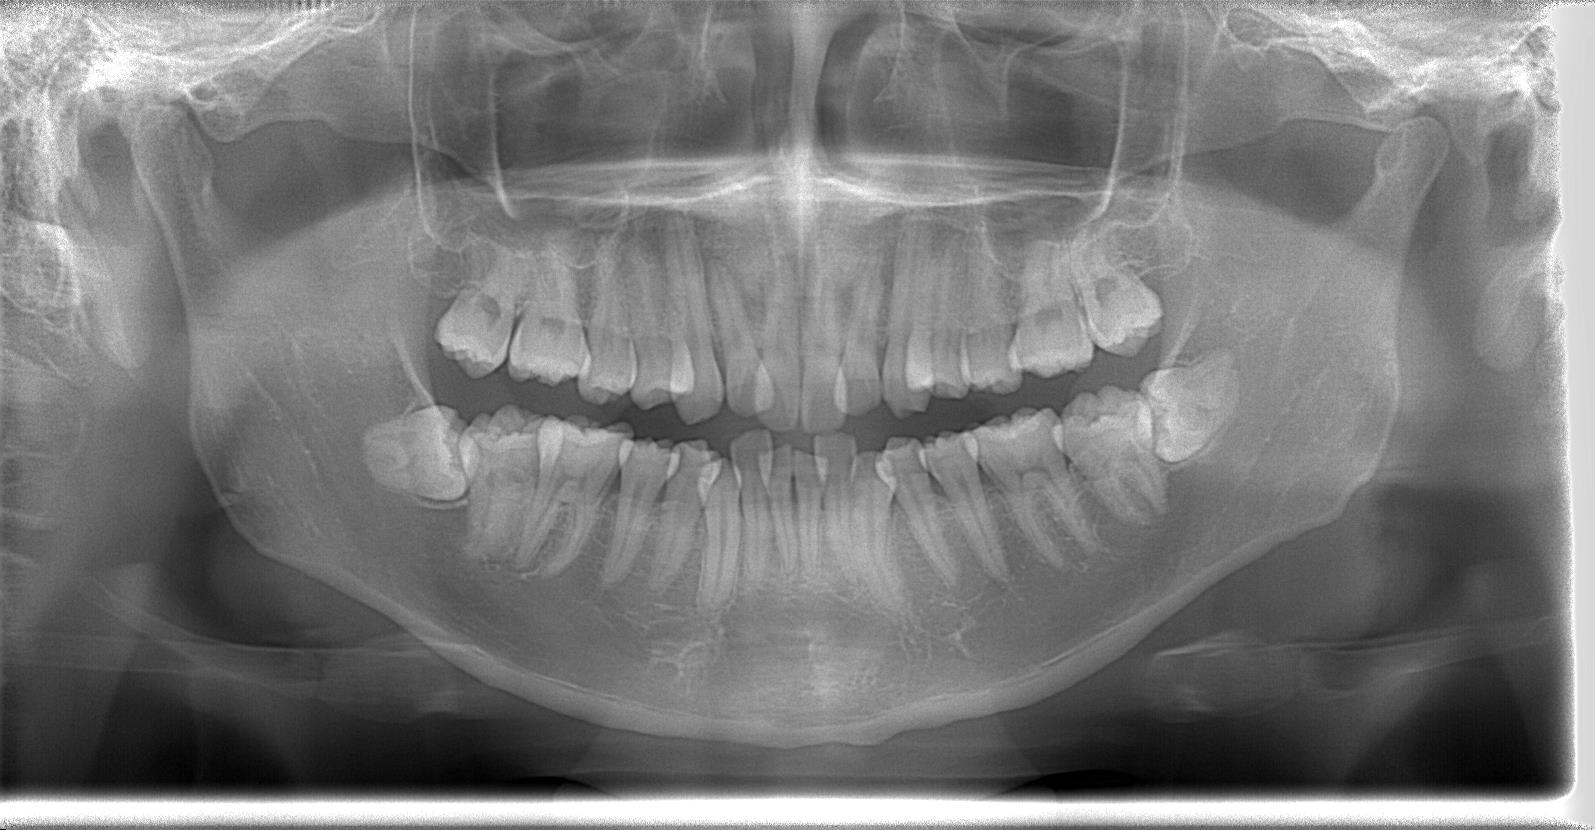

[術前パノラマレントゲン写真]

第3大臼歯を抜歯して矯正配列している症例です。